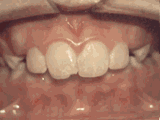

Phase I

Patient's parents were concerned about both aesthetics and the health of the erupting permanent teeth when they brought him to the orthodontist at age eight. The lower front teeth were crowded and they touched the palate, and the upper front teeth were extremely displaced from their normal positions. After twenty months of Phase I treatment with an expander and partial braces, patient's appearance and dental function was vastly improved.